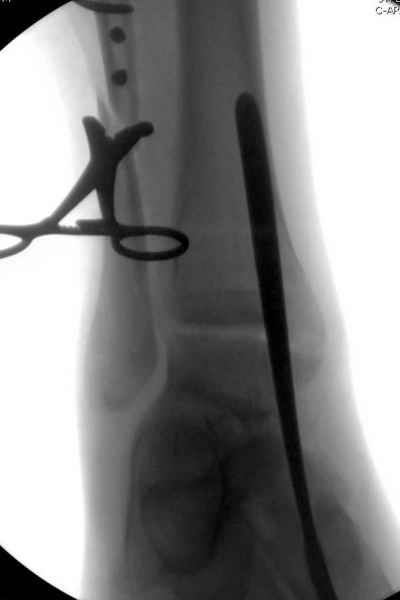

С мнением «провести позиционный межберцовый винт чуть ниже пластинки в положениий тыльного сгибания стопы» согласен, но я бы нагрузку начал через три недели и удаление шурупа можно провести через 6-8 недель.

Для облегчения удаления сломанных шурупов (случается часто) рекомендую фиксацию двумя 3.5мм кортикальными шурупами на 3 мм длиннее, тот же сломанный шуруп легко удаляется с медиальной стороны.

Здесь похожий случай трехнедельной давности, перелом почти сросся и была укорочена малоберцовая, на операции длину малоберцовой смогли восстановить только после того, когда проксимальнее пластины ввели шуруп и использовали его как толкатель, с помощбю дистракционого инструмента (lamina spreader).

Меньше всего волнует положение медиальной лодыжки - в любое время можно провести остео или реостеосинтез, при несращении можно просто резецировать без ущерба для движений в голеностопе. Здесь обошлись фиксацией одним 4 мм канюлированным шурупом.